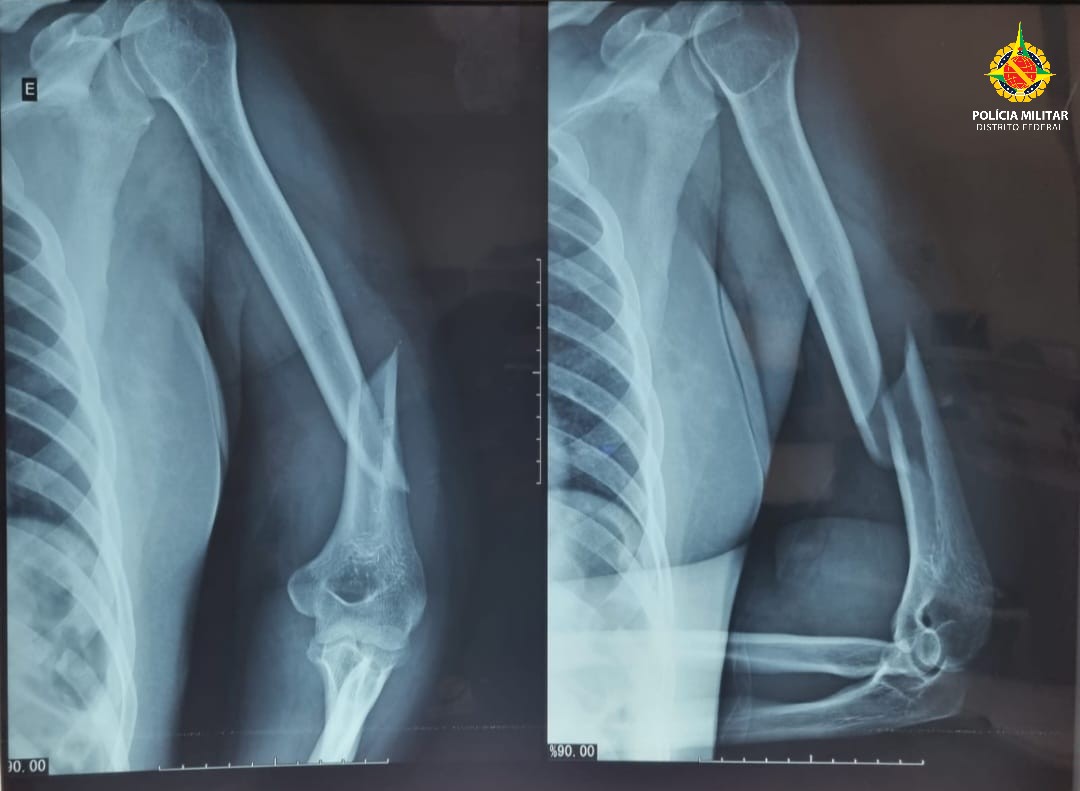

A equipe foi acionada via COPOM para atender uma ocorrência de violência doméstica. No local, a vítima apresentava hematomas no rosto, inchaço ao redor dos olhos, sangramento pelos ouvidos, fratura no úmero esquerdo e luxação no ombro esquerdo. Segundo informações do SAMU, o quadro clínico é sugestivo de trauma cranioencefálico (TCE).